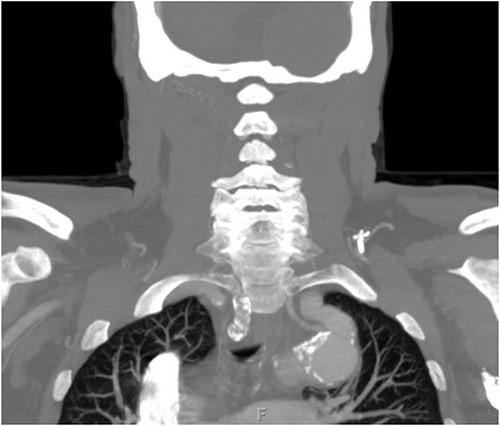

The patient is a 70-year-old male with an incidental finding of a proximal LSA aneurysm on computed tomography (CT) angiography of the chest performed for shortness of breath. He had no dysphagia, neurologic or vascular occlusive symptoms. He had no history of trauma or known congenital anomaly. The aneurysm had a maximal diameter of 3.4 cm and was located at the origin of the artery (Fig. 1). An aberrant left vertebral artery and hypoplastic right vertebral artery were also identified. The left vertebral artery originated from the aortic arch proximal to the LSA takeoff (Fig. 2) and provided dominant posterior cerebral circulation.

Preoperative CTA demonstrating aberrant left vertebral artery originating from the aortic arch, just proximal to the LSA.